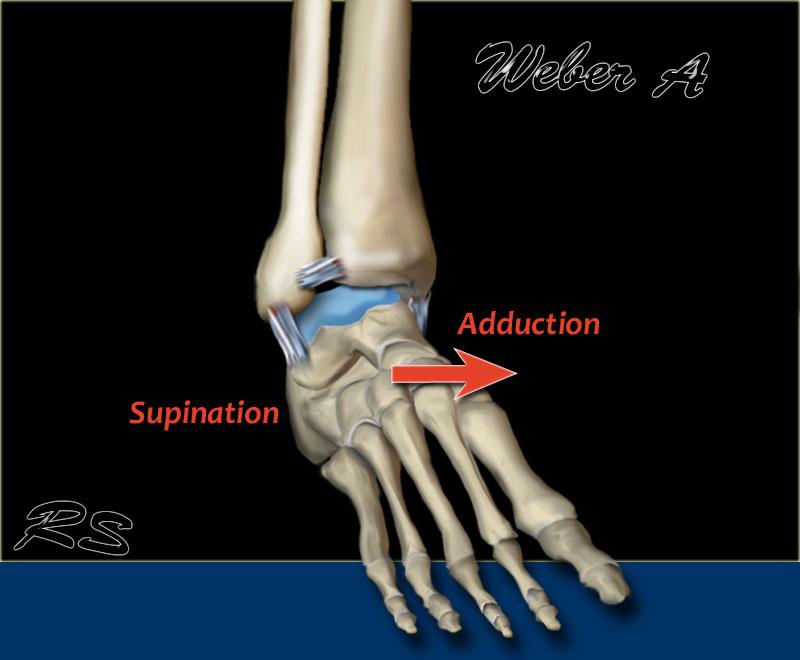

Weber A

Xảy ra dưới khớp chày mác, khớp này còn nguyên vẹn.

Theo Lauge-Hansen, đây là kết quả của lực khép tác động lên bàn chân ở tư thế sấp.

- Giai đoạn 1 – Lực căng lên các dây chằng bên ngoài dẫn đến đứt dây chằng

hoặc gãy giật (avulsion) mắt cá ngoài ở dưới khớp chày mác. - Giai đoạn 2 – Gãy chéo mắt cá trong.

Theo Lauge-Hansen, gãy xương này xảy ra do lực khép tác động lên bàn chân ở tư thế ngửa.

Mặt ngoài chịu lực căng cực độ kéo giãn các dây chằng, dẫn đến gãy xương do giật avulsion.

Hầu như luôn luôn, gãy xương avulsion xuất hiện dưới dạng đường gãy ngang.

Kiểu này được gọi là gãy xương kiểu kéo ra (pull off), trái ngược với kiểu đẩy ra (push off), vốn xuất hiện dưới dạng đường gãy chéo hoặc dọc.